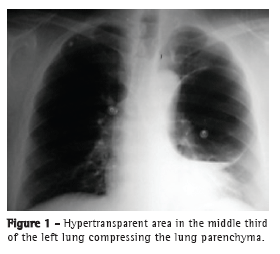

The patient was admitted to an emergency room with intense chest pain and sudden-onset dyspnea during air travel. Immediately after admission, electrocardiography was performed and cardiac enzyme levels were determined. The electrocardiogram and cardiac enzyme levels were found to be normal. A chest X-ray revealed a round hypertransparent area located in the middle third of the left lung and compressing the lung parenchyma (Figure 1). An axial CT scan of the chest confirmed the presence of a hypertransparent area occupying the entire anterior segment of the left upper lobe and measuring 12.2 × 9.0 cm, as well as containing a fine liquid layer. No other changes were found. The patient underwent left thoracotomy with selective lung intubation. We found a lung bulla located in the upper lobe and occupying the entire mediastinal surface of the lung. The affected area was resected and stapled with a mechanical stapler, and abrasion pleurodesis was performed. No other macroscopic changes were observed during the surgical procedure. After the surgical procedure, the patient was transferred to the ICU, where he was woken and extubated. The postoperative evolution was favorable, the chest tube having been removed on postoperative day 5. A follow-up chest X-ray revealed re-expansion of the left lung and hypotransparent areas in the middle third, which were attributed to the edema and the hematoma at the suture site. The histopathological features of the surgical specimen were found to be consistent with cystic adenomatoid malformation.